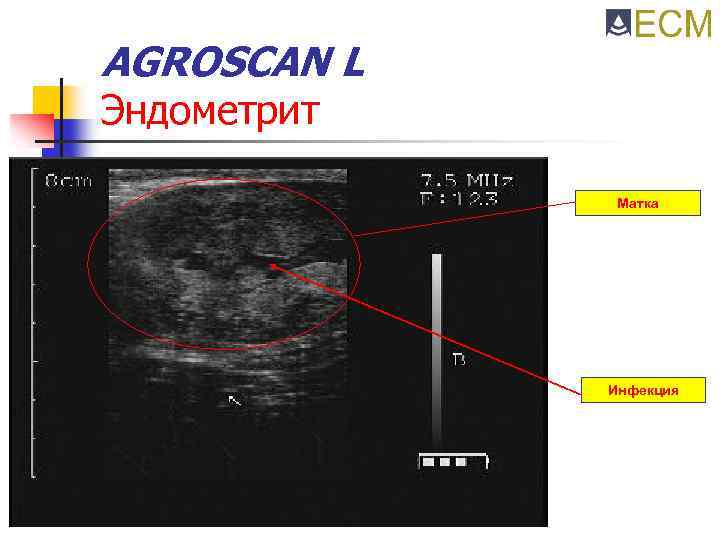

AGROSCAN L Эндометрит Матка Инфекция